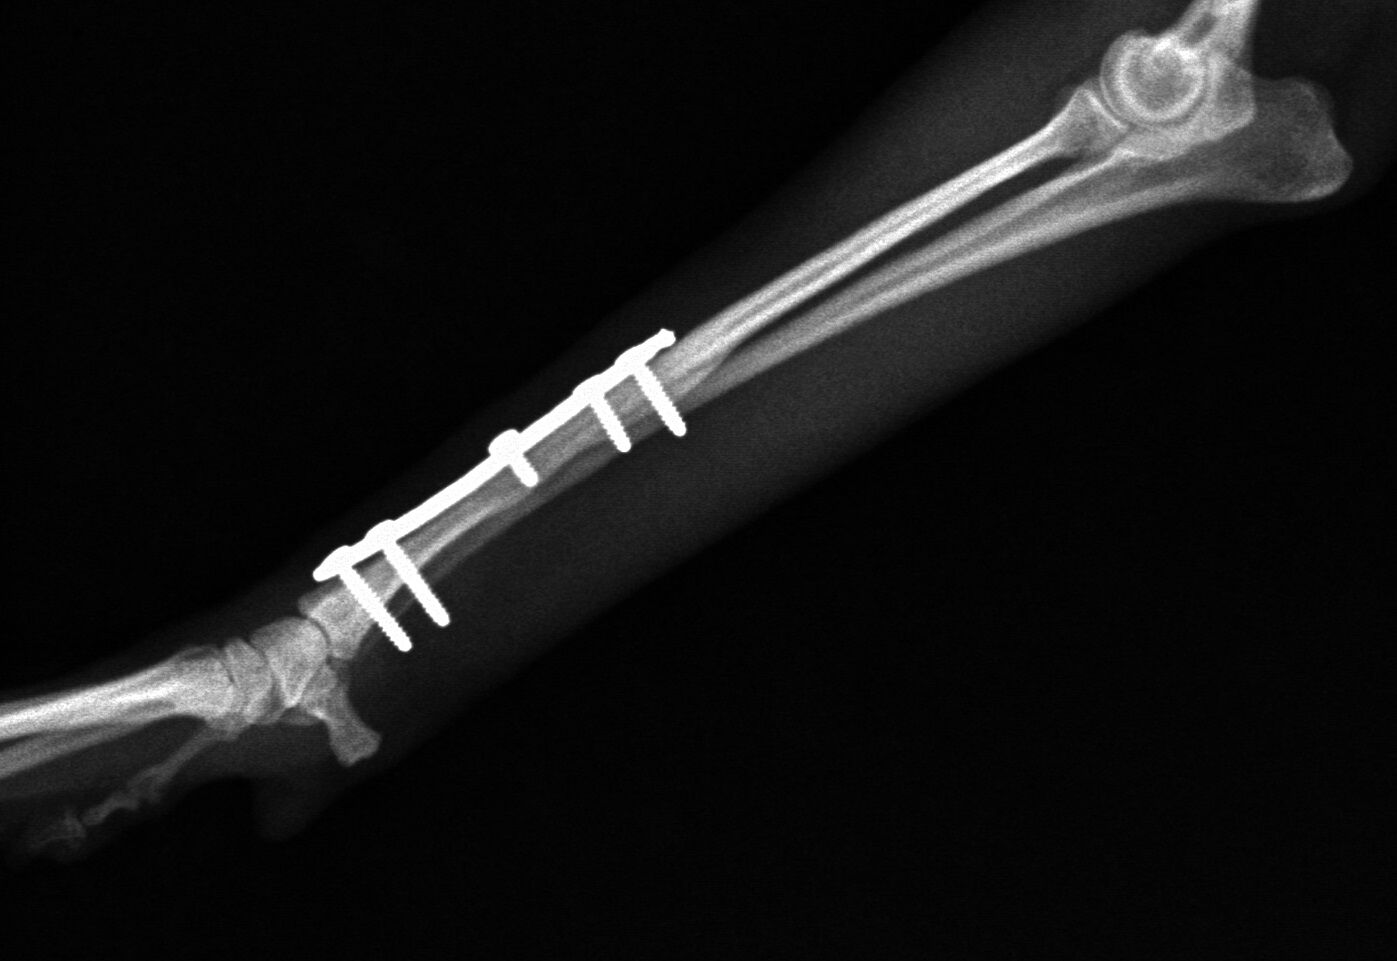

手術後1か月は外固定で補助します。その後、レントゲンで問題ないことを確認し外固定を外しました。外した後は普通に歩行し、散歩なども普段通りにしてもらいます。獣医師によってはプレートを残したままにすることがありますが、中にはプレート部分の骨が細くなってしまうことがあります。もし仮にプレートが折れてしまった時には大変な手術が必要になることがあります。当院では高齢犬であればプレートを残したままにするのですが、この症例は若かったので上記の心配もありますので、プレートを除去することにしました。ただトイ・プードルは骨の増生が良くないことが多いので、プレートを外した直後に再骨折したということがよくあります。ですので、当院ではプレートを留めているスクリューを段階的に外していきます。下の写真は手術後3か月の時に一部のスクリューを取った写真です。

スクリュー除去前 骨折面は消えています。

スクリュー除去後